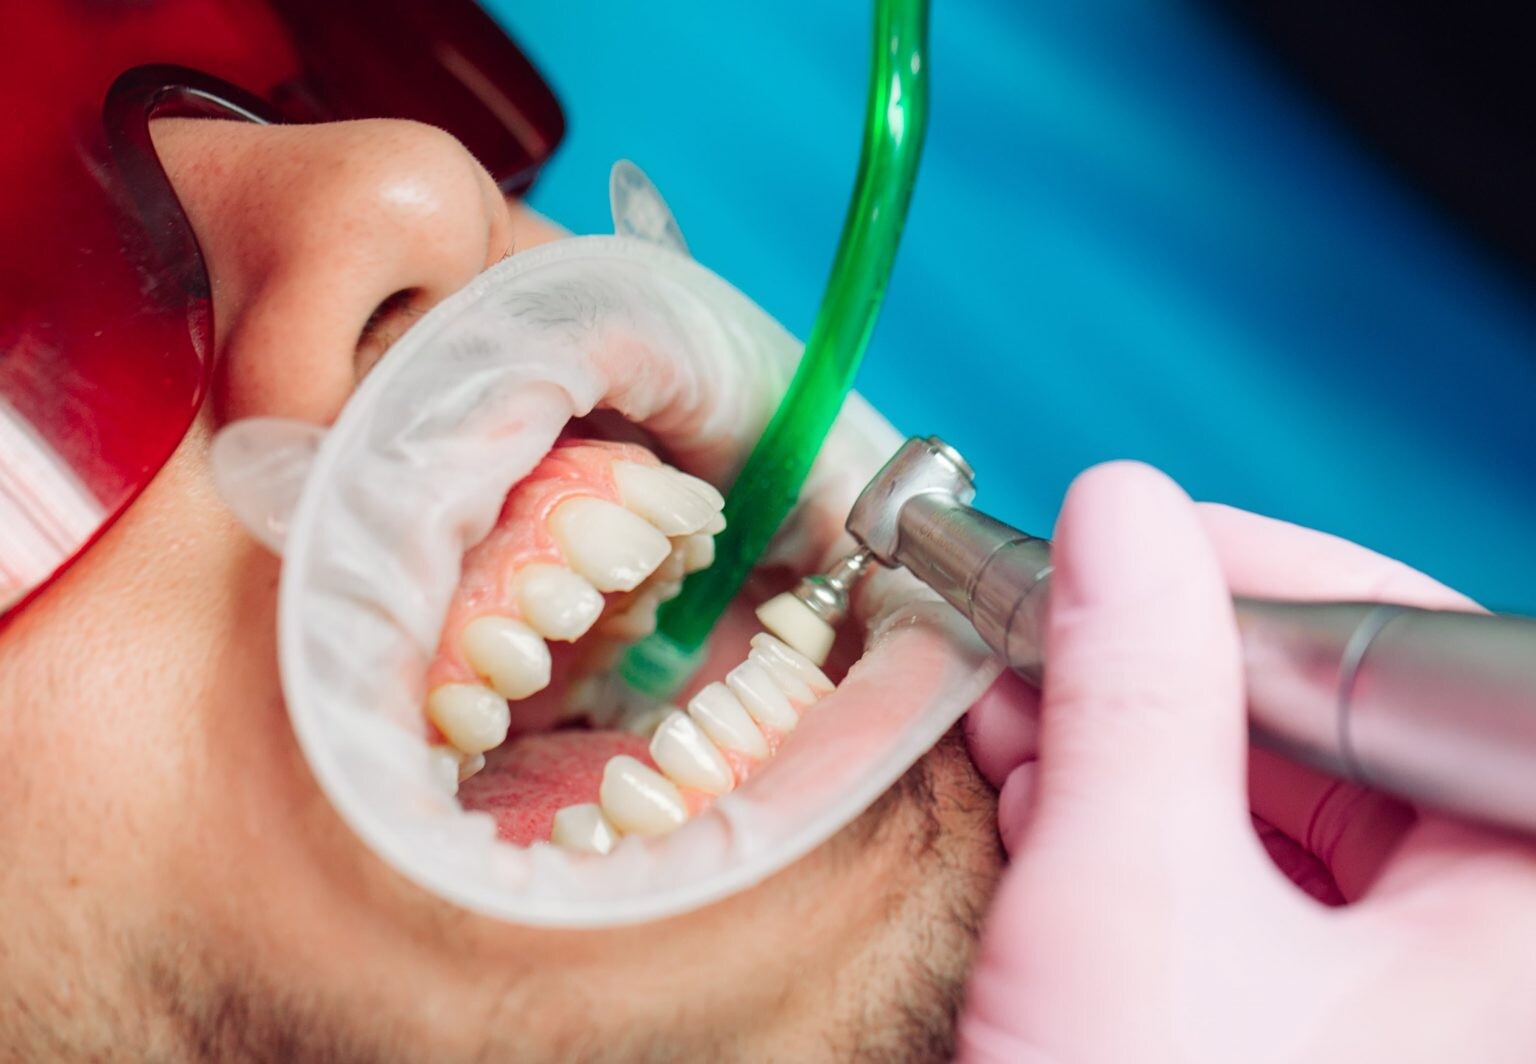

Regularly scheduled dental cleanings are crucial in keeping your teeth and gums healthy.

A prophylaxis treatment is a technical term for regular teeth cleaning. Prophylaxis appointments and proper at-home oral care can contribute to a radiant smile and overall well-being.

This article explores what dental cleaning entails, and what you can expect during a prophylaxis session.

Prophylaxis dental cleaning, is a preventive dental procedure to remove plaque, tartar, and stains from the teeth and gums.

Prophylaxis dental cleaning is an essential part of maintaining optimal oral health.

This procedure is typically performed by a dental hygienist or a dentist in a dental office.

A dental prophylaxis session usually involves several steps to ensure thorough cleaning of your teeth and gums.

During a teeth cleaning appointment, you can expect the following procedures:

Examination: The dental professional will comprehensively examine your mouth before the cleaning begins. This examination helps identify oral health issues and determine the appropriate treatment plan.

Plaque and Tartar Removal: Using specialized dental instruments, the dental hygienist or dentist will carefully remove plaque and tartar deposits from your teeth. They will focus on areas that are hard to reach during regular brushing and flossing.

Teeth Polishing: After plaque and tartar removal, the dental professional will polish your teeth using a rotating brush or a rubber cup with an abrasive paste. This step helps remove surface stains and leaves your teeth looking clean and shiny.

Flossing and Rinsing: Once the teeth are polished, they will floss between your teeth to remove any remaining debris or plaque. They may also ask you to rinse your mouth to remove any residual polishing paste or debris.